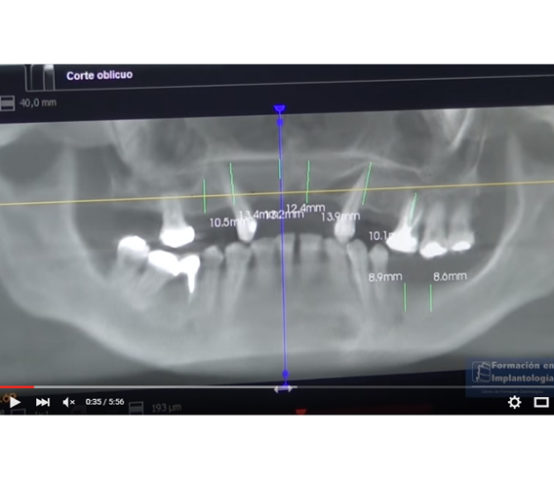

12.C. Avanzada.Carga inmediata.8CIL.EXT+Provisional+Sedación

Implantes Proclinic Formación en Implantología.

En este vídeo que forma parte de la Formación Proclinic en Implantología, se realiza la colocación de 8 implantes cilíndricos externos marca Proclinic + electrosoldadura intraoral.